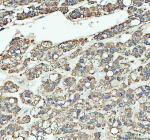

Immunohistochemical staining of ARHGEF12L using anti-ARHGEF12L antibody. ARHGEF12L was detected in a paraffin-embedded section of human liver cancer tissue. Heat mediated antigen retrieval was performed in EDTA buffer (pH 8.0, epitope retrieval solution). The tissue section was blocked with 10% goat serum. The tissue section was then incubated with 2 ug/ml rabbit anti-ARHGEF12L antibody overnight at 4oC. Peroxidase Conjugated Goat Anti-rabbit IgG was used as secondary antibody and incubated for 30 minutes at 37oC. The tissue section was developed using an HRP secondary and DAB substrate.